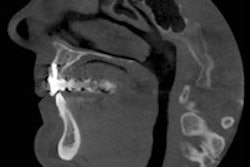

A wide variety of factors figures into healing potentials. In general, the two most important factors are the type of injury and the degree of root development, said Linda Levin, DDS, PhD, vice president of the American Association of Endodontists.

"A classic study on 400 patients with more than 600 luxated teeth followed over 10 years reveals that pulp necrosis is related mainly to the type of injury and the stage of root end development. Pulp necrosis and, therefore, infection increase with the extent of injury," Dr. Levin said, citing a 2006 study by Frances Andreasen, DDS, Dr Odont, and colleagues in Dental Traumatology (April 2006, Vol. 22:2, pp. 99-111).

"According to Frances Andreasen, concussion and subluxation represent the least risk, followed in ascending order by extrusive, lateral, and intrusive luxation," she said.